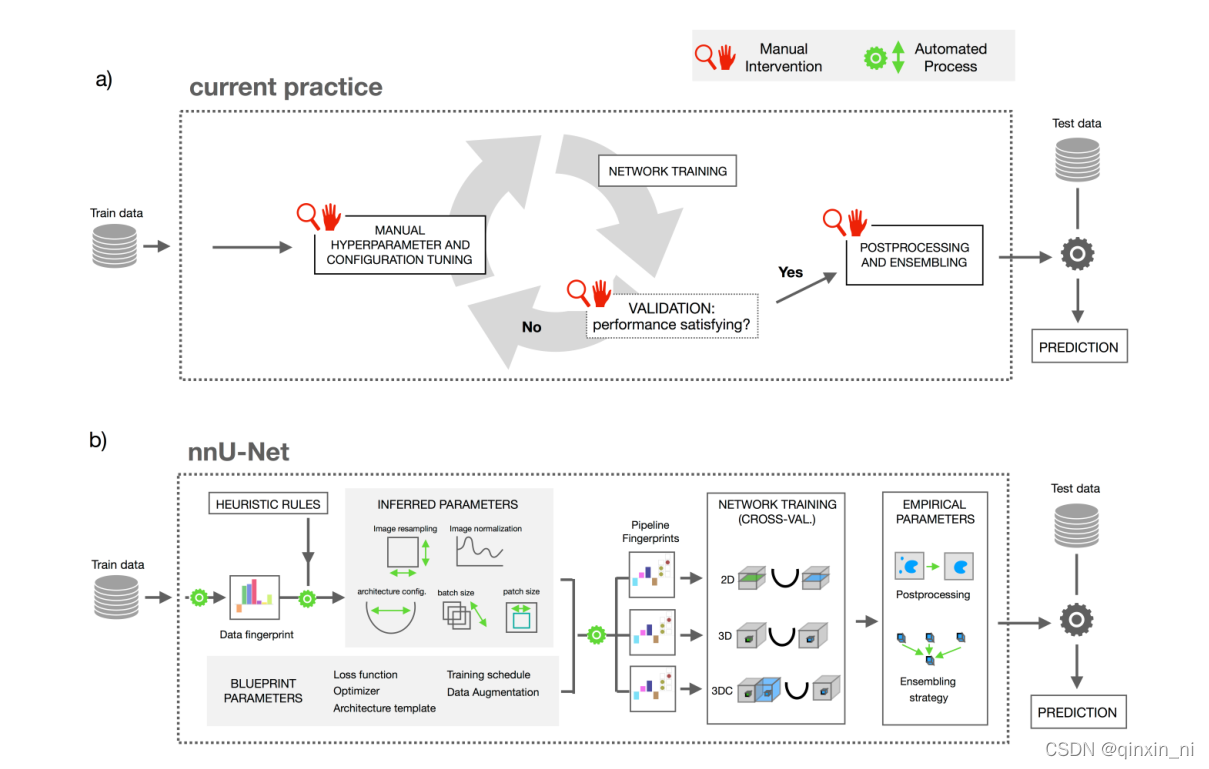

下图a代表了现在根据专家知识和实验修正的模型设计思路,针对于任务,

b代表nnUnet的设计思路,定义了dataset fingerprint和pipeline fingerprint。Dataset fingerprint是数据集的关键表征,比如图像大小、体素空间信息和类别比例;Pipeline fingerprint被分为三组:blueprint、inferred和empirical参数。Blueprint代表基本的架构设计,比如U-Net类的模板、损失函数、训练策略和数据增强;Inferd代表对新数据集的必要适应进行编码,并包括对确切的网络拓扑、补丁大小、批次大小和图像预处理的修改。数据指纹和inferd之间的关系是通过执行一组启发式规则建立的,当应用于看不见的数据集时,无需进行昂贵的重新优化。通过对训练案例进行交叉验证,可以自动确定empirical参数。默认情况下,nnU-Net会生成三种不同的U-Net配置:一个2D U-Net、一个以全图像分辨率运行的3D U-Net和一个3D U-Net级联。交叉验证后,nnU-Net会根据经验选择性能最佳的配置或整体。

1) 最近普遍的深度学习的步骤:进行迭代式的训练和调参,训练之后评估结果,效果不好则进行调参,调参之后继续训练,最终进行侦测,反复如此;

2) nnUNet:

1.数据【无论是训练数据还是测试数据,都具有相对应的属性,即指纹】的属性会被总结成一种“数据指纹”;

2.一系列的启发式的规则会推理出适合这种指纹的“管道”(由蓝图参数(计划参数)推理得出):

3.上一步推理出的参数,例如image resample、batch_size等,联合起来成为“管道指纹”:

4.2D、3D和3D_Cascaded三个网络分别训练,得出各自的模型(三个网络结构共享一个“管道指纹”,五折交叉验证)

5.选择出最优的模型进行推理(可以单个进行推理,也可以三个模型一起进行推理)

上图(a)展示了近来的多数医学图像分割是如何进行一个新的数据集的训练的。这个过程是“专家驱动”的,而且需要长时间的人为的试错的过程,显然,这样的训练方式对于手头上要处理的数据可能极少有先兆的参考。上图(b)中nnUNet却将这个自适应的过程系统化。

因此,我们在此定义了一个类似于“图片大小”这样的标准数据集的属性——dataset fingerprint(数据指纹),和一个pipeline fingerprint(管道指纹)[一个训练计划中各个配置的合体]。对于一个给定的“数据指纹”,nnUNet负责生成一个指定的“管道指纹”。

- 在nnUNet中,这些“管道指纹”被分为蓝图参数、推理参数和经验参数

- 蓝图参数:

- 基础的网络架构选择:比如一个朴素的nnUNet网络;

- 易于选择的一些表现较好的常用超参数:比如损失函数、训练进度表、数据增强方式;

- 推理参数

- 对一个新数据集进行适应性的编码,包括新的网络拓扑结构、patch_size、batch_size和图像预处理

- 数据指纹’和‘管道指纹’两者之间的关系可以通过执行一系列启发式的规则来进行建立,而且遇到未知的数据集时也不需要昂贵的反复训练的代价;

- 注意许多的设计选择都是相互依赖的

- nnUNet卸去了人为解释这些依赖关系的压力

- 经验参数:经验参数只会在后面的推理时使用,这点从上图b可以看出

- 2D、3D、3D-cascade

- 2D-Unet: 普通的2D-Unet

- 3D-Unet: 对一整张图片像素进行操作

- 3D-cascade: 级联网络:第一个网络对下采样图片进行操作,而第二个网络对前一个网络产生的结果在整个图片的像素上进行调整。

- 在进行完交叉验证之后,nnUNet会经验性的选择表现最好的参数,可能是独个的推理结果,也可能是一起推理的结果。在结果可以评估的情况下,把对次优效果的抑制作为一项后处理操作。